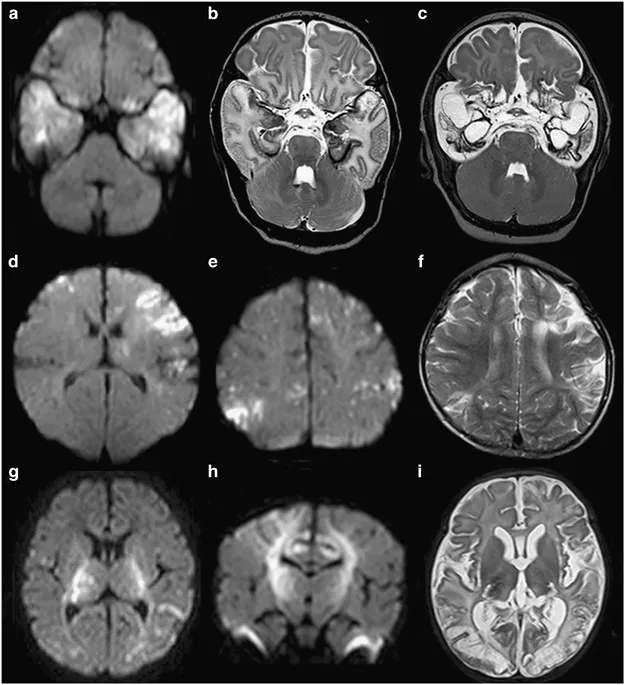

- Imaging (CT/MRI): Basal exudates, hydrocephalus, tuberculomas, infarcts.

| Imaging | Temporal lobe hemorrhagic necrosis | Thalamic, basal ganglia involvement |

- Japanese Encephalitis shows extrapyramidal features and bilateral thalamic lesions.